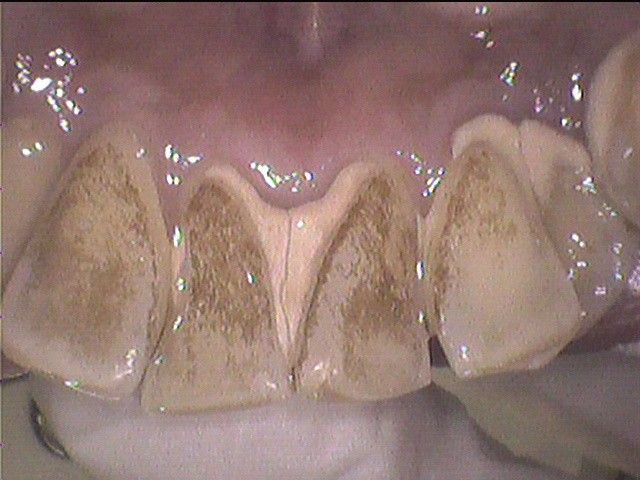

3歳の子供の前歯が茶色くなってきました。麦茶を飲ませているからでしょうか? 3歳検診の時に簡単に落としてもらったのですが、まだ気になります。 きれいに落とすことはできるのでしょうか? 歯医者さんにはかかったことがないので不安ですが大丈夫でしょうか?. あります!! それは・・・ 今度、紹介します(。・ε・。) ここで症例を一つ(上の前歯の裏から撮影) 3年前に、(写真で右上の)前歯を「 セラミック 」で治療した. 市販品で頑固なヤニを落とすには時間がかかるんです。 「一刻も早くきれいにしたい」そんなあなたには 歯医者に行って自費の「着色汚れを除去する“クリーニング”」 をおすすめします。.

デンタルタイムズ V Twitter 前歯の裏にベットリついた着色汚れを落とす 今回の患者さんは前歯の裏側に着色汚れがべっとりとついていました 超音波チップを使って 汚れをはじき落としていきます T Co Yvyhnswpo1 デンタルタイムズ 歯医者 着色汚れ

前歯の裏にベットリついた着色汚れを落とす Remove Stains On Teeth Youtube